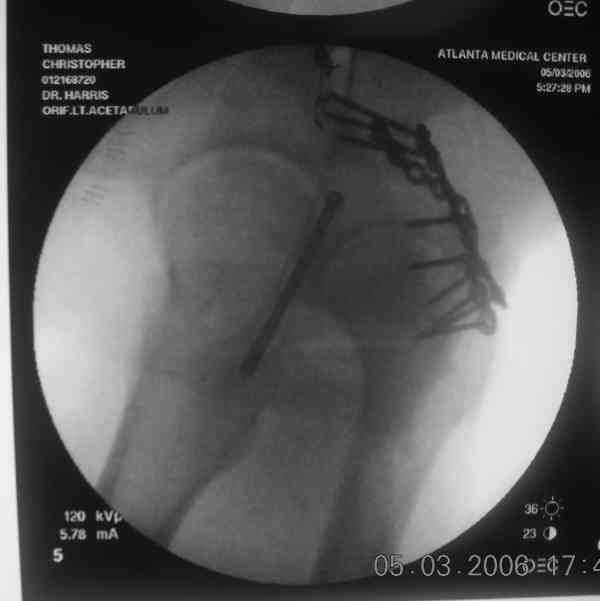

I'll include a few images of a similar injury in a similarly large male patient. This patient "showed up" in our ER c/o hip pain 2 months after being treated in the lateral position, without a quality reduction, without an anterior column transverse supporting implant, with an unbalanced plate applied too medially, with insufficient caudal segment fixation...it took over 8 hours and a 3+ l blood loss to debride the callus from front then

back, excise the HO, release his sciatic nerve, reduce the head-transverse-wall, and fix it...and now it's a staging procedure.

the case that I found is a 20yo male, MCC. his AP pelvis shows an interesting position of his bladder. it is pushed aside by a hematoma from SGA injury. we did a limited lateral window approach for the anterior column first, pt bumped up/supine. then closed and repositioned for KL. I could not find intra-op photos of cases when we did only a small incision for the AC screw (but they do exist!!). the lateral window is available for reduction assessment if a KL approach is being used. in the lateral position this window is available. the prone position definitely takes pressure off of the post column and facilitates reduction. in the lateral position a schantz pin in the ischial tub +/- bone hook in sciatic notch helps with PC reduction. the lateral position also gives better airway access for anesthesia. airway problems are rare, but prone position seems to be a bit more of a challenge to exchange the tube, or reintubate altogether. just something further to debate!

dan schlatterer

atlanta

[ Ответить ]